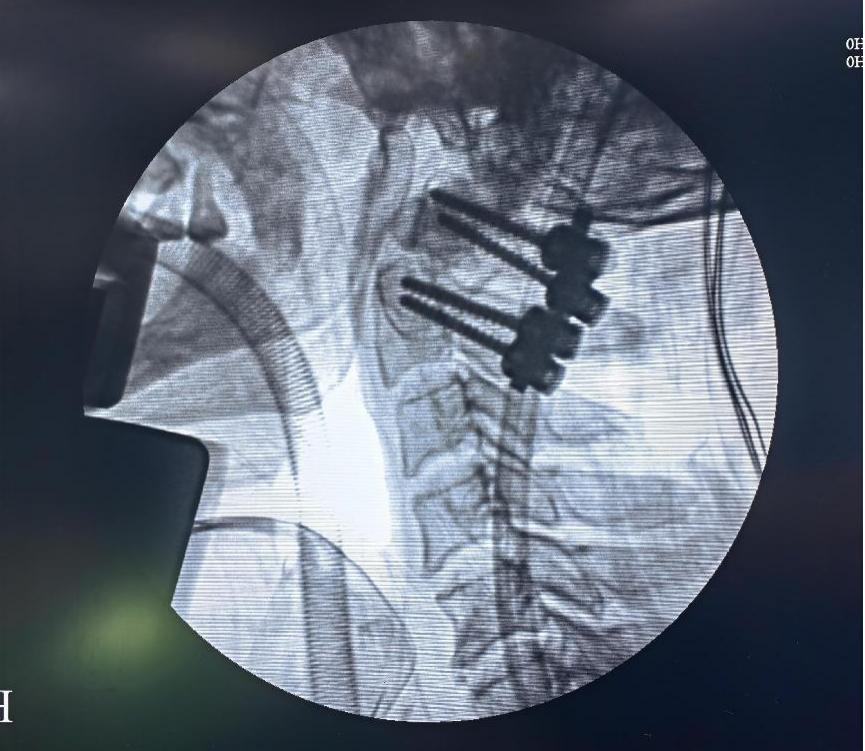

术中定位:四枚螺钉,精准置入到位